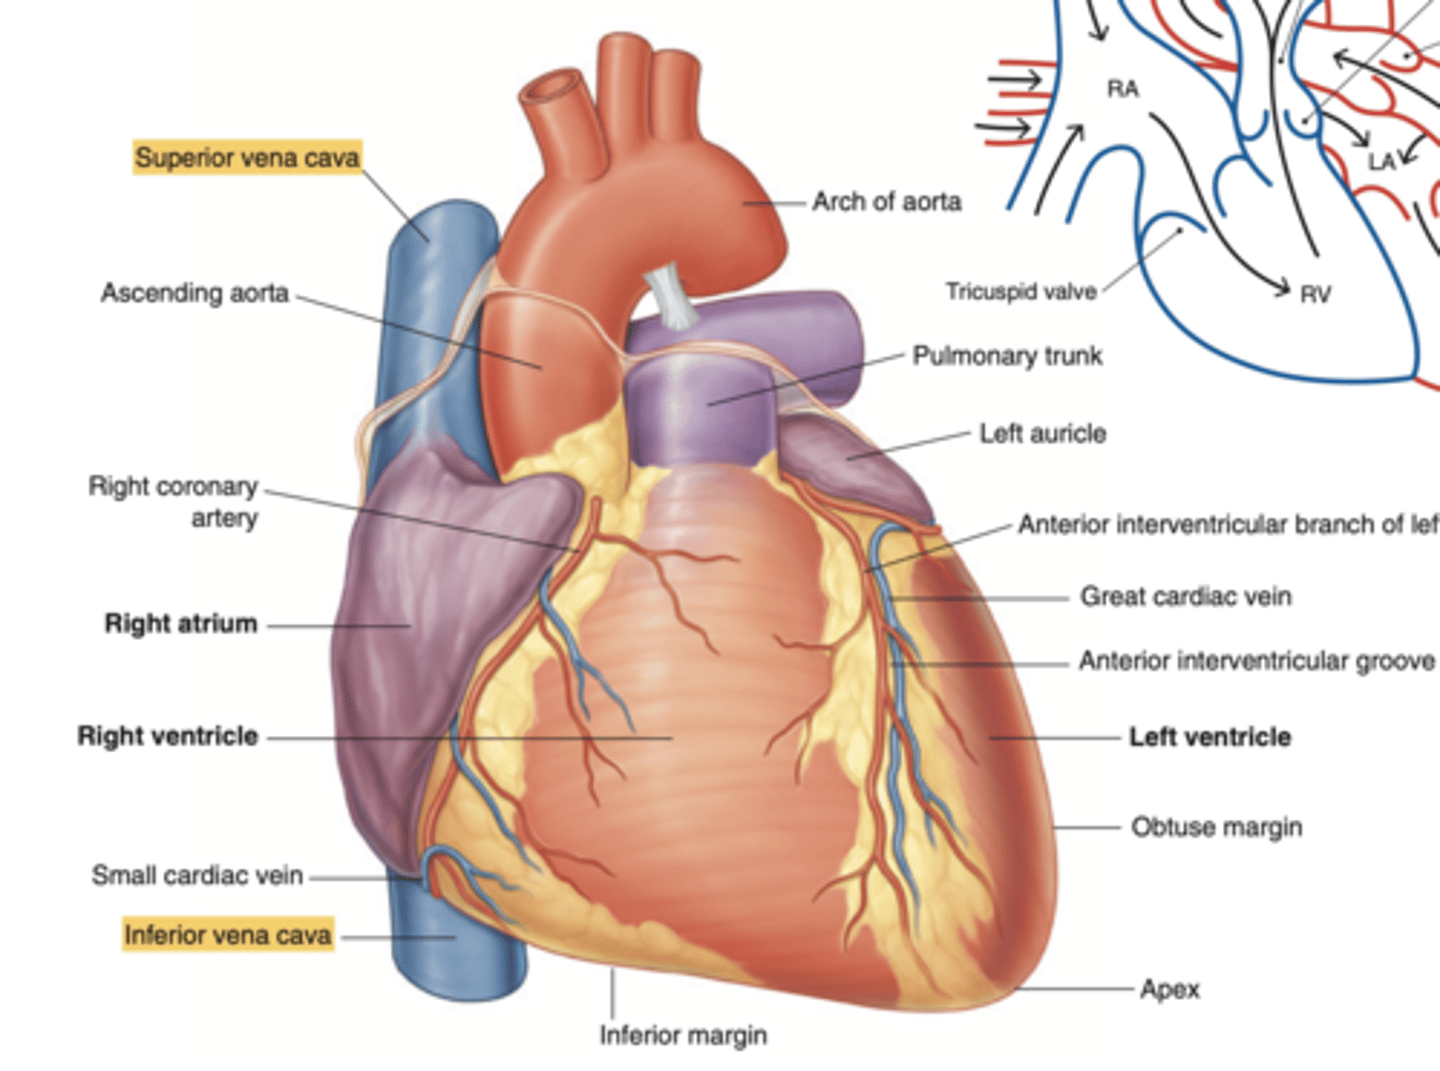

How is the heart's shape described and what are its surfaces?

The heart has an inverted pyramidal shape lying in one side.

Surfaces:

. Inferior diaphragmatic surface

. Sternocostal surface or anterior surface (corresponds mainly to the right ventricle)

. Posterior surface (corresponds to the ventricles, mainly to the left one)

. Right pulmonary surface

. Left pulmonary surface

Describe the apex in the heart's anterior view

. Point to left side, downwards.

. At the level of the 5th intercostal space (we will auscultate the apex of the left ventricle)

Describe the Sternocostal Surface

Most of the anterior surface of the heart corresponds to the right ventricle.

Describe the location of the main arteries in the anterior view of the heart

The pulmonary trunk exits the right ventricle

. aorta exits the left ventricle.

What is the pulmonary trunk?

. major blood vessel that plays a crucial role in the circulatory system by carrying deoxygenated blood from the heart to the lungs.

. Divides into left and right pulmonary arteries

What structures enter the right atrium posteriorly?

. Superior Vena Cava (SVC)

. Inferior Vena Cava (IVC)